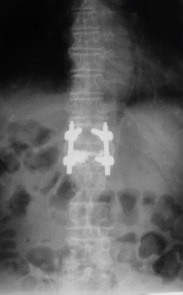

辅助检查:MRI检查示腰1椎体骨质疏松性压缩性骨折。

诊断:腰11椎体骨质疏松性压缩骨折

治疗:因患者椎体压缩骨折明显,椎体后缘骨折不完整,突入椎管,且硬膜囊受压,因此不适合行椎体成形术。给予单节段椎弓根钉固定并椎板切除减压术。骨折椎置钉结合钉道骨水泥加强稳定性。术后随访效果满意。

随访未见内固定松脱,无矫正丢失。